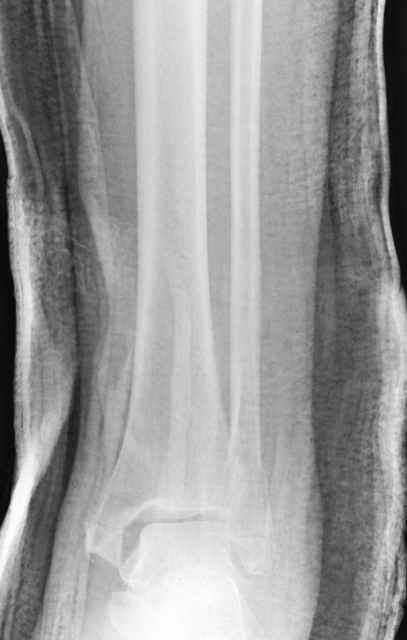

Pilon fracture:

-Появляется ориентир и остов, на чем можно строить восстановление, почему сперва малоберцовую, впервые обьяснили и описали (Pylon type and Ankle fractures) в середине 50х Rienau и Gay.

Восстановливая длину и ротацию малоберцовой кости, затем относительно легче произвести реставрацию остальных элементов перелома дистального эпиметафиза болшеберцовой кости.

где исследования на трупах показали, что малоберцовая кость участвует в стабильности голеностопного сустава, поддерживая наклон тарана (talar tilt) за счет связок. После ознакомления работой Ramsey в ортопедию ввели термин "при переломах голеностопного сустава смещенная

таранная кость следует за малоберцовой костью" т.е. связка не рвется, а тянет таран за собой, поэтому восстановление малоберцовой кости в

первую очередь, затем остальных элементов - стал классическим при лечении данной патолгии. Латеральная колонна (столб), дистальный

конец малоберцевой кости, к нему прикрепляется латеральный суставной фрагмент дистального эпиметафиза большеберцовой кости (как на снимке)

и таранная кость, которые при репозиции малоберцовой кости репонируются автоматически.

Из работ Ramsey and Hamilton, Yablon et., укорочения на 1мм

малоберцовой кости, уменьшает на 42% контактную поверхность между

малоберцевой и таранной кости, которое в свою очередь приводит к

увеличению давления на остальные части суставной поверхности, что

является предпосылкой раннего артроза.

The unsatisfactory clinical results sometimes associated with slight widening of the ankle mortise and 42% reduction in the area of contact

between the tibia and talus with one millimeter of lateral displacemet emphasize the importance of restoring the normal roentgenographic relationship of the talus to medial malleolus after ankle

injures. Since the stress per unit area increases as the total area decreases, a decrease in contact area may be a factor contributing to a poor result after ankle or dislocation when talar displacement is one millimeter or more.